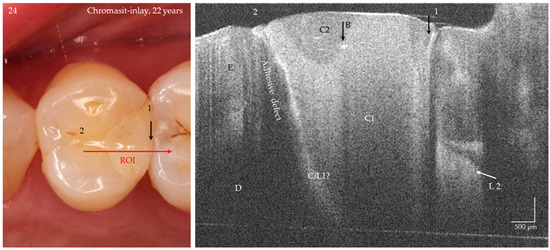

Caries, the world’s most common chronic disease, remains a major cause of invasive restorative dental treatment. To take advantage of the diagnostic potential of optical coherence tomography (OCT) in contemporary dental prevention and treatment, an intraorally applicable spectral-domain OCT probe has been developed based on an OCT hand-held scanner equipped with a rigid 90°-optics endoscope. The probe was verified in vitro. In vivo, all tooth surfaces could be imaged with the OCT probe, except the vestibular surfaces of third molars and the proximal surface sections of molars within a "blind spot" at a distance greater than 2.5 mm from the tooth surface. Proximal surfaces of 64 posterior teeth of four volunteers were assessed by intraoral OCT, visual-tactile inspection, bitewing radiography and fiber-optic transillumination. The agreement in detecting healthy and carious surfaces varied greatly between OCT and established methods (18.2–94.7%), whereby the established methods could always be supplemented by OCT. Direct and indirect composite and ceramic restorations with inherent imperfections and failures of the tooth-restoration bond were imaged and qualitatively evaluated. The intraoral OCT probe proved to be a powerful technological approach for the non-invasive imaging of healthy and carious hard tooth tissues and gingiva as well as tooth-colored restorations. Full article

Figure 1